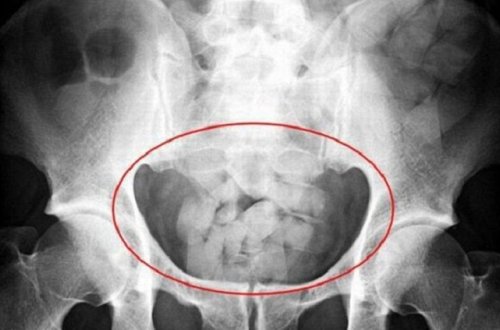

İran vətəndaşının düz bağırsağından çıxanlar hər kəsi təəccübləndirdi -

FOTO

400

gömrük

7news

üçün

zamanı

vasitə

ədəd

vətəndaşın

nəzarətindən

narkotik

biləsuvar

xəstəxanasına

mərkəzi

rayon

aparılıb

müayinə

tibbi

müşayiəti

yarandığı